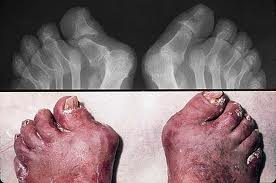

Two-thirds of patients with psoriatic arthritis have an asymmetric oligoarthritis or a monoarthritis, but others have polyarticular disease that mimics osteoarthritis or rheumatoid arthritis in its distribution. Involvement of the distal interphalangeal joints, which are spared by rheumatoid arthritis, can help distinguish psoriatic arthritis from rheumatoid arthritis. Psoriatic arthritis of the distal interphalangeal joints is associated with abnormalities of the nail bed and dystrophic changes of the nail, such as pitting, onycholysis, ridging, and brown-yellow discoloration (oil-drop sign).

Psoriatic arthritis has a distinctive radiographic appearance, specifically the concurrence of both bony destruction and proliferation at an affected site . In addition, psoriatic arthritis can be highly destructive, with development of a pencil-in-cup appearance of the finger bones, and in some cases, arthritis mutilans. Involvement of the axial skeleton resembles that of reactive arthritis. Sacroiliitis is usually unilateral, and nonmarginal syndesmophytes characterize the spondylitis.

nails in psoriasic arthritis skin psoriasic arthritis